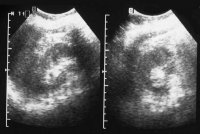

Neben der Anamnese, körperlicher Untersuchung, Messung des Blutdruckes sowie der Laboruntersuchungen: Urinstatus, Serumkreatinin und -Elektroylte ist die Sonographie zur Feststellung einer einseitig kleinen Niere zielführend (Abbildung 10a). Zur Diagnostik zählt fernerhin die NFZG (Abbildung 10b) bzw. Computertomographie.

Die Abbildungen zeigen die Anwendung von Sonographie und Miktionszysturethrogramm bei einer kleinen stummen Niere (Abbildung 13, 14).